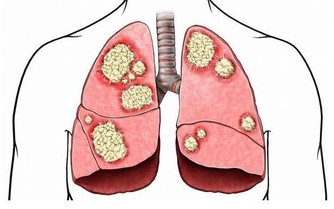

臨床上,另一名50多歲民眾,檢查出貧血症狀,且腎臟功能異常被轉診至醫院,確診為多發性骨髓癌,經過標靶藥物合併化學治療後,貧血症狀也逐漸改善;林明恩醫師說,若抽血檢查被告知有貧血現象,就應提高警覺,必要時就應進一步接受檢查。